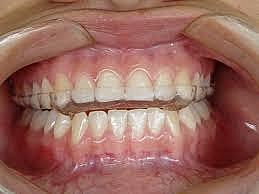

Se realizó la toma de modelos como protocolo para una correcta valoración y estudio del paciente; como también la toma de fotografías de estudio intraorales del maxilar y mandíbula. En estas fotografías intraorales se encontró que el paciente tiene el frenillo labial superior extendido. Lo que ha provocado el diastema en el paciente.